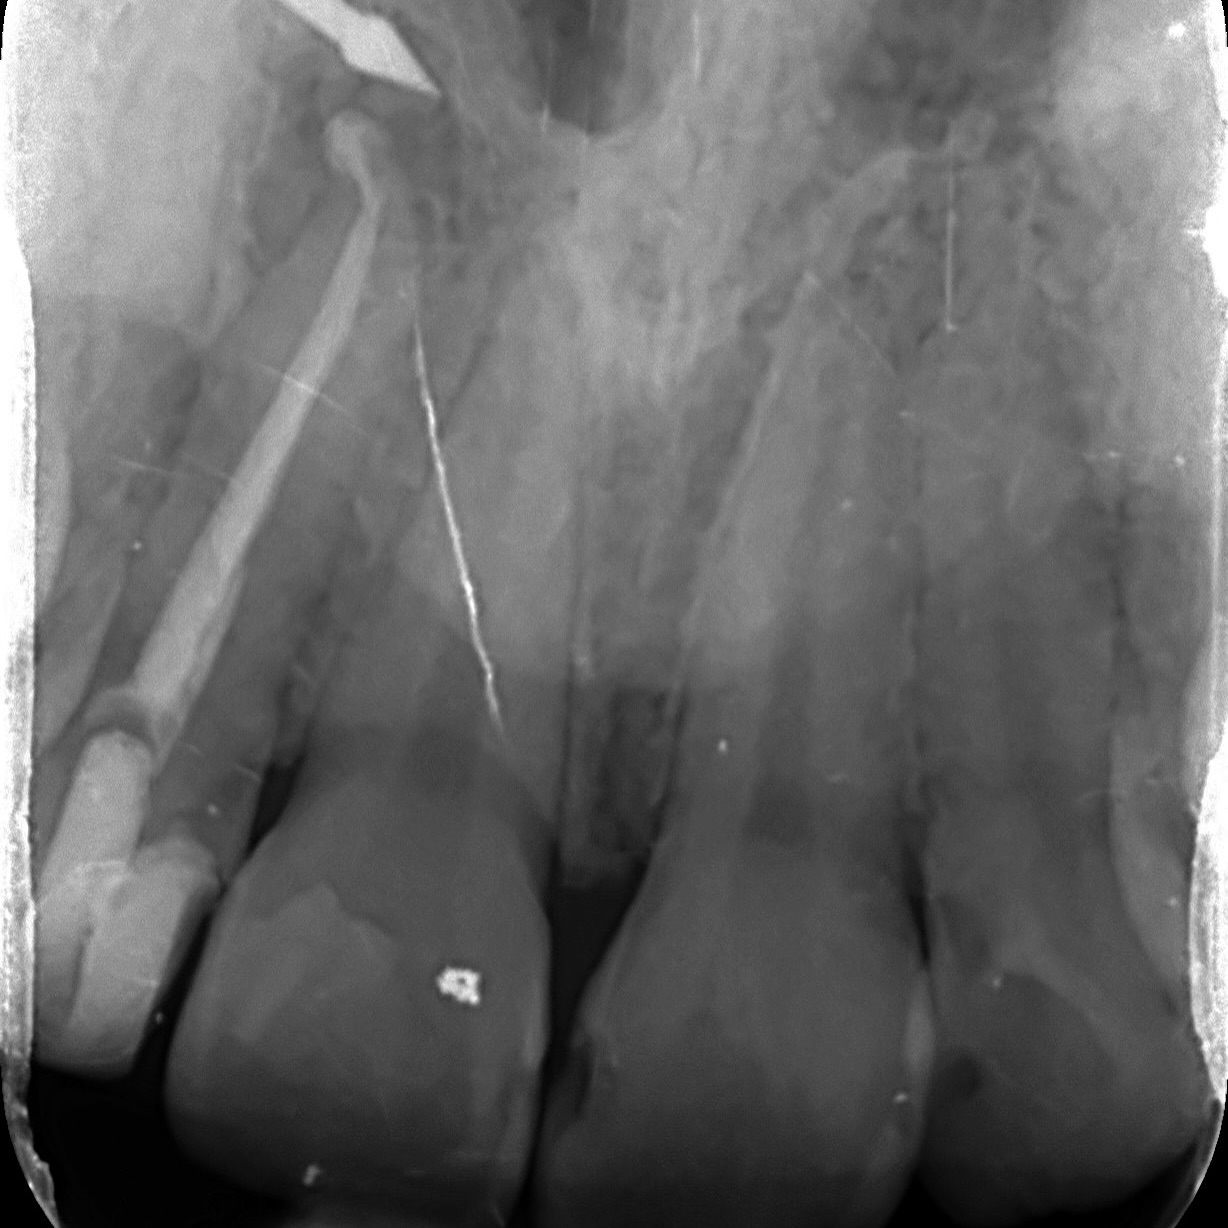

A comprehensive, non-specialist referral service for dental patients requiring affordable Endodontic treatment

Information regarding our services can be found here